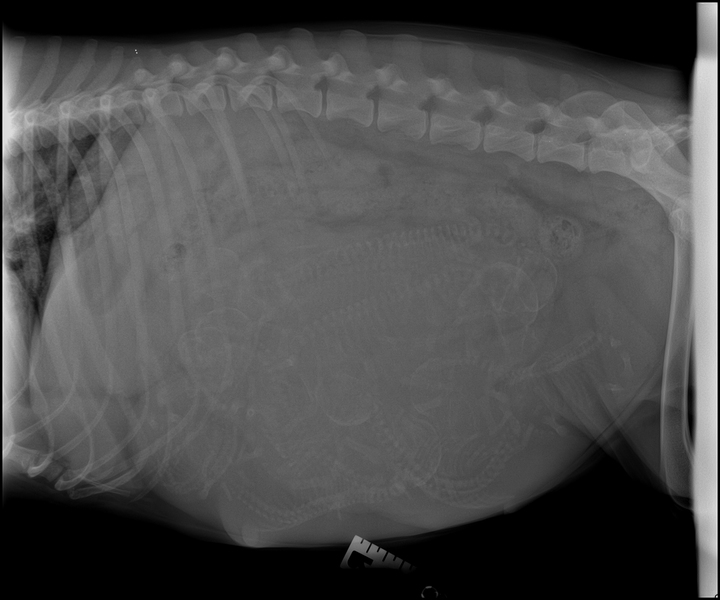

Enter Sandman Litter:

Co Litter: 5 Girls and 2 Boys

Born August 3rd

Champion Slash Dad and Love is All Around Litter Mom